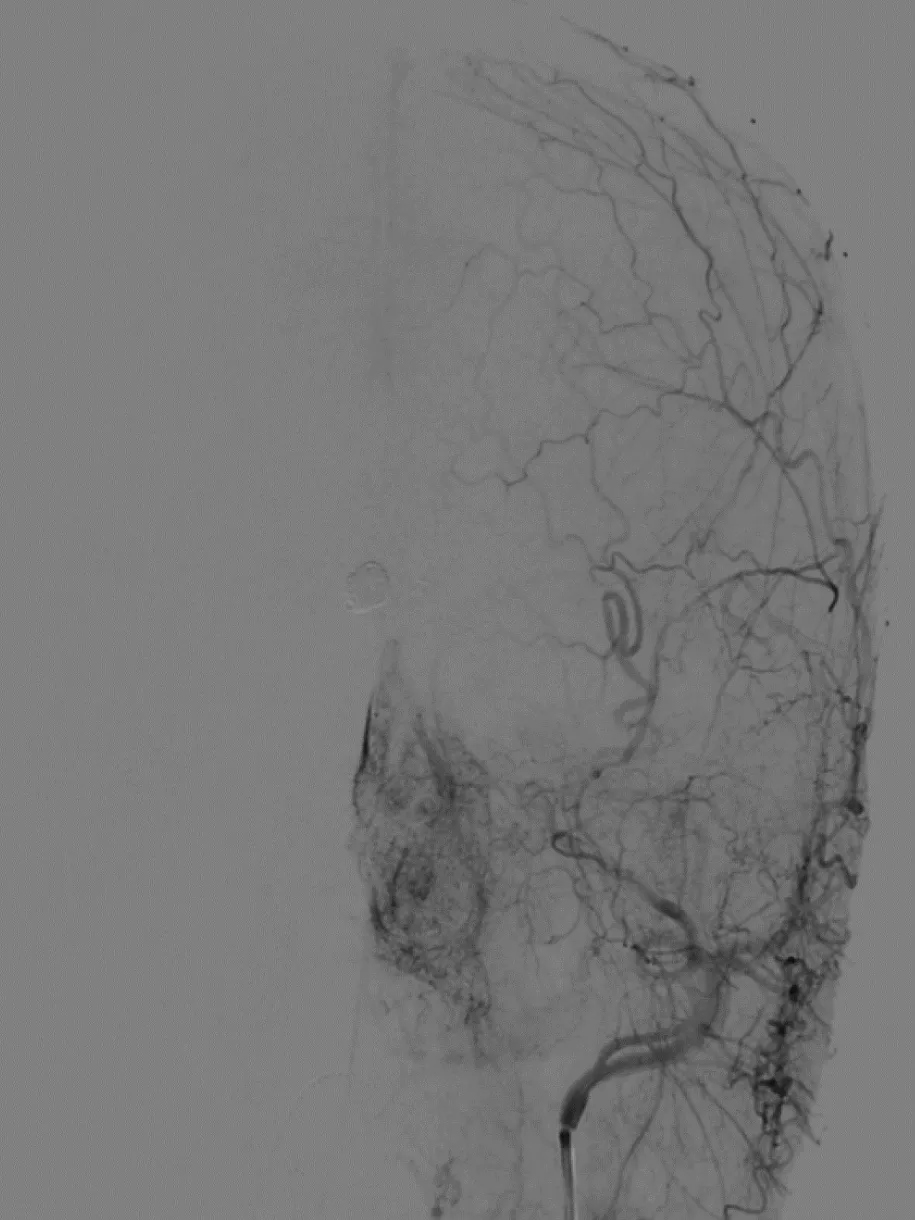

术前造影

左颈总造影,未见异常供血

右颈外造影,可见右侧蝶腭动脉分支供血,但无良好路径显示

右颈内造影,可见右侧眼动脉-筛后动脉供血,见经额底静脉-双侧额部皮层静脉向上矢状窦方向引流

经右眼动脉工作路径

SONIC微导管到位后,手推造影确认

SONIC微导管造影证实

首次注胶

首次注胶后造影仍见瘘口区显影

继续注胶,见部分反流,停顿

停顿等待后继续注胶

造影显示瘘口消失

拔管过程,见SONIC微导管头端解脱

拔管后造影:

SONIC微导管头端解脱,右侧眼动脉显影良好,未见拔管牵拉痉挛表现

可见SONIC微导管可解脱头端显影

术后即刻,供血分支、瘘口区及引流静脉完全消失,不显影。